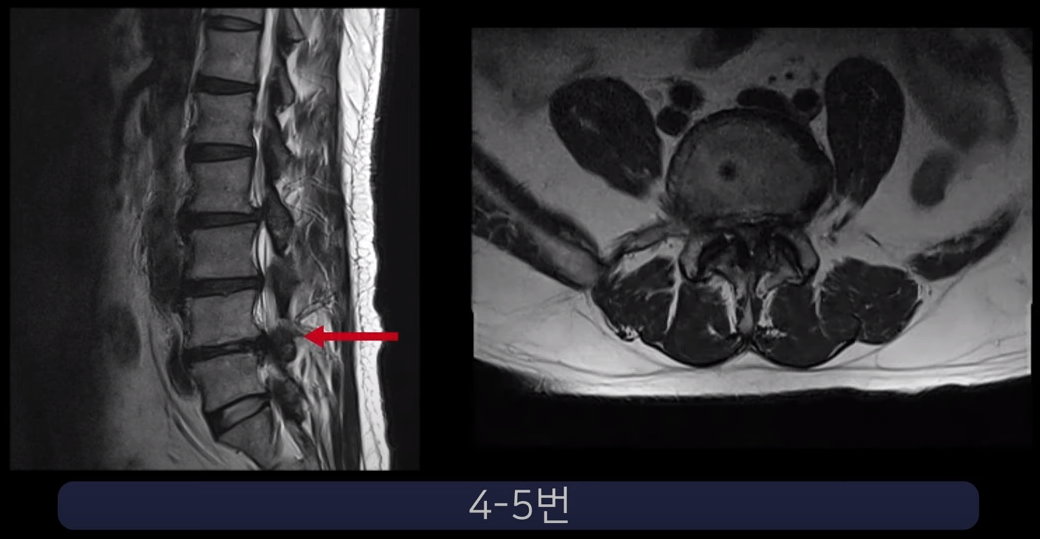

실제 척추관과 추간공이 심하게 막힌 두 환자 케이스를 보여드리겠습니다.

첫 번째 환자분입니다. 이 환자분은 허리 세 마디에 심한 협착이 있습니다. 2-3번, 3-4번, 4-5번 이렇게 척추관이 세 마디가 심하게 막혀있습니다.

25년간 허리에 신경주사를 맞아왔는데 이젠 효과가 전혀 없고, 작년부터 거의 걷지 못하는 상태가 되어 수술을 결심하였습니다. 대학병원에서 수술이 어렵다고 했고 유명 척추병원에서 3주에 걸쳐 3번의 수술을 권했습니다.